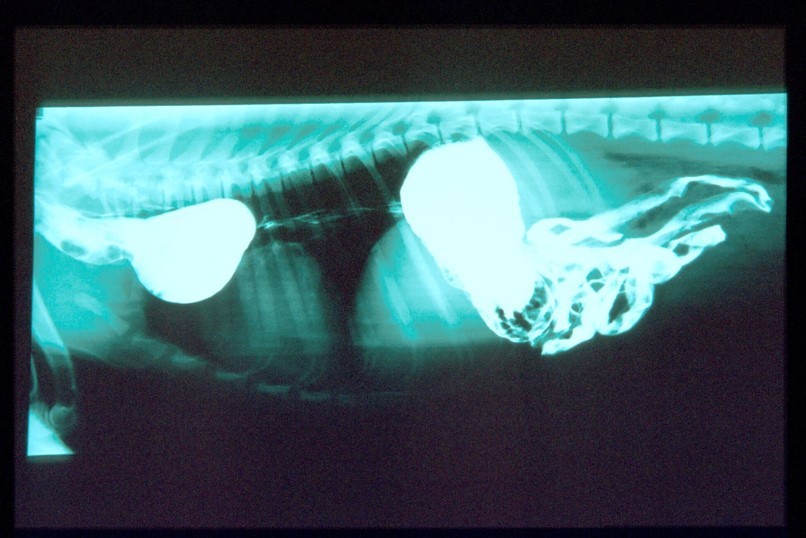

What does this show?

RA haemangiosarcoma